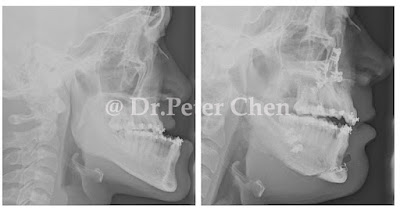

前陣子有個軍人來找我,主要的問題是下顎骨突出(戽斗)所造成的前牙開咬,只有後排幾顆牙齒碰得到。他吃東西非常不方便,也因此常被長官罵說怎麼吃東西這麼慢,因為不敢吃太久,體重一直過瘦。

他屬於嚴重型前牙開咬 ( Anterior open bite ) 的案例,不做手術很難用單純矯正改善。在我提出治療計畫後,他問了我一句 "醫師,是不是很嚴重?手術是不是很困難?"

一年多前,我遇過一位跟他很像的病人,大概是我目前碰過前牙開咬最嚴重的,上下排牙齒差了近2公分。

他是住在新加坡的馬來西亞華人,自己一個人來台北諮詢,也是擔心自己的情況是太嚴重,手術很複雜困難。

前兩天他特別從新加坡飛來看我,感覺胖了一點,我想是因為咬合正常了,吃東西也方便多了吧!?

療程效果因人而異,上圖為該案例實際術後成效